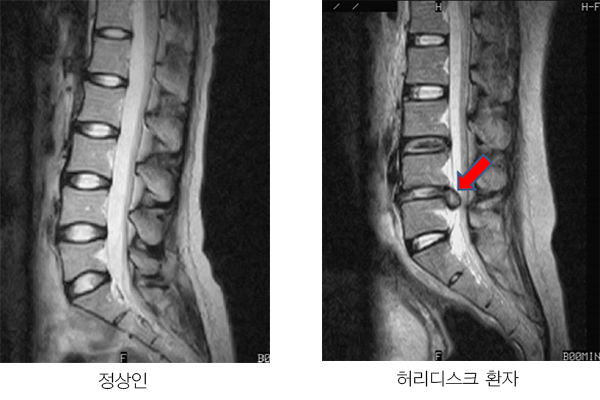

허리디스크에 대해 아직 살펴보지 못하셨다면 허리디스크가 어느 부위를 말하는지 확인하시고 시기에 맞추어 운동하여 주십시요.

서울대 재활의학과 교수님이 쓴 책의 내용인데 1주일에 20km 이상을 달리는 사람과 운동은 하지 않는 사람들을 비교해 봤을 때, MRI 영상에서 달리기를 꾸준히 하는 사람들이 허리디스크가 두꺼웠고 그 속의 수분 함유하고 있는 분량이 높았다는 내용이 있었습니다.